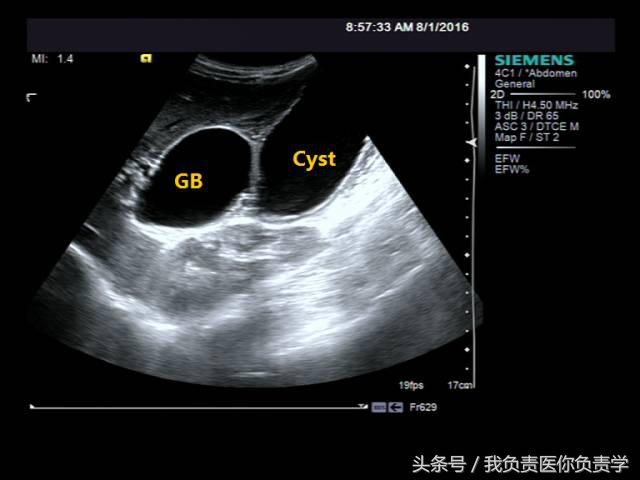

患者男,64岁,因右上腹疼痛半月余就诊。查体发现右上腹部轻压痛,无发热。超声检查所见如下:

图2示于胆囊外侧可见一局限性囊性无回声区